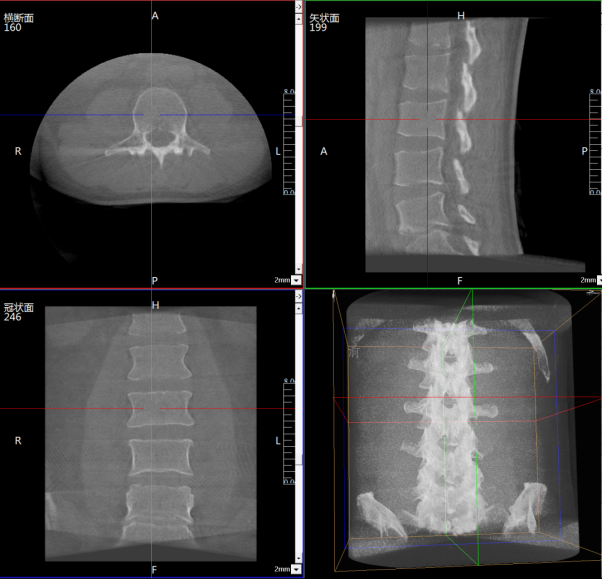

Perlove Medical’s flat-panel 3D C-arm has been introduced to the Pain Management Department of Anning First People’s Hospital, supporting the development of spinal endoscopic surgery.

Spinal surgeries in pain management focus on neuromodulation, requiring precise planning of the puncture path while carefully avoiding blood vessels, nerve roots, and visceral structures.Given the complex anatomy of nerves and blood vessels surrounding the spine, the inherent superimposition of structures in conventional 2D imaging may cause misinterpretation.

The 3D C-arm can generate intraoperative three-dimensional spinal images and CT-like cross-sectional views, providing physicians with a more comprehensive perspective for observation and clinical diagnosis.